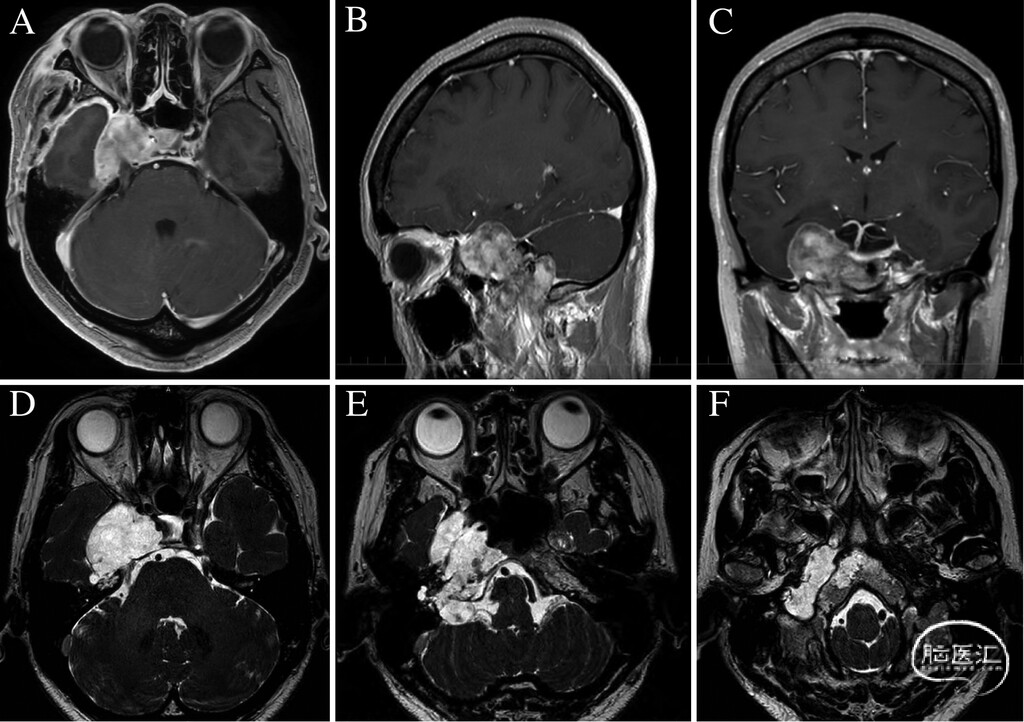

图1:外院术前MRI。A-C:钆增强T1加权像,显示巨大颅底肿瘤及肿瘤在左侧上颌骨内的广泛侵犯。D-F:FIESTA显示肿瘤在脑桥(D)、延髓(E)、枕髁(F)层面的受累情况,清晰呈现病变与脑干及颅底结构的毗邻关系。

● 入院时,患者仍存在远距注视复视,右侧传导性听力下降持续存在,证实为轻度浆液性中耳炎伴传导性听力下降。MRI示一大小约6 cm的分叶状肿块,累及以下区域(图2A-D):海绵窦及Meckel腔、岩尖与颞骨岩部、颈静脉孔、内听道后方的CPA、枕髁及舌下神经管外侧的颅外颅底。肿瘤在T1WI呈低信号,T2WI呈高信号,FLAIR呈稍高信号,水肿轻微,强化不均匀。CT骨窗示内听道下方沿颞骨岩部长轴广泛骨质侵蚀(图3)。DSA示除脑膜垂体干有少量供血外,无其他主要供血动脉。右侧海绵窦及乙状窦功能性闭塞,静脉回流主要经乳突导静脉。